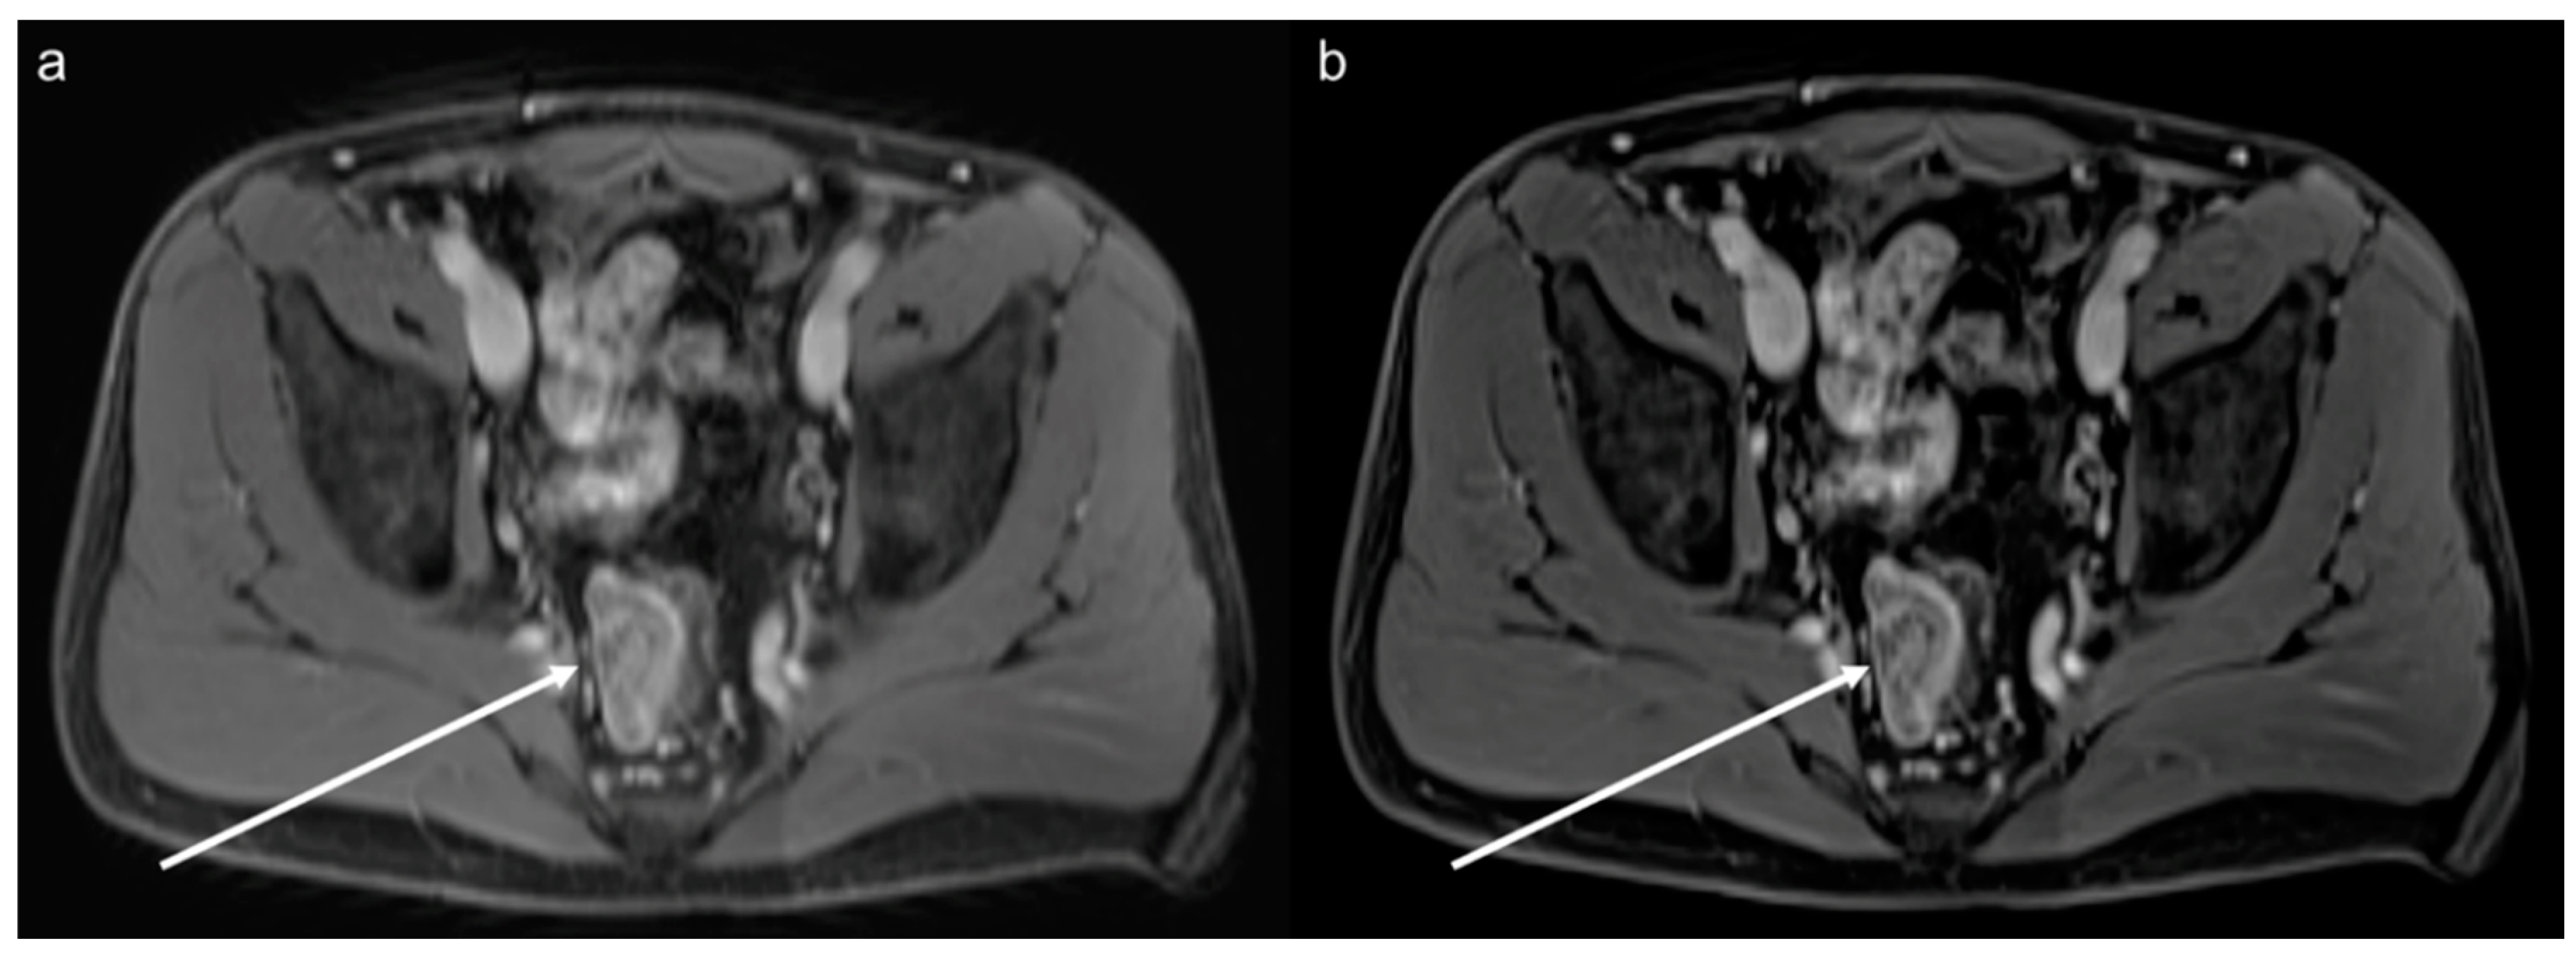

3.3. Qualitative Results of the Precontrast Images

3.4. Qualitative Results of the Postcontrast Images

3.5. Lesion Assessment